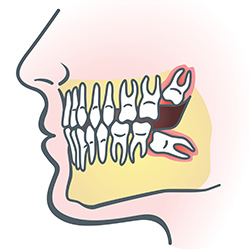

Wisdom teeth are molars found in the very back of your mouth. They usually appear in the late teens or early twenties, but they may become impacted (fail to erupt) due to lack of room in the jaw or angle of entry. When a wisdom tooth is impacted, it may need to be removed. If it is not removed, you may develop gum tenderness, swelling, or even severe pain. Impacted wisdom teeth that are partially or fully erupted tend to be quite difficult to clean and are susceptible to tooth decay, recurring infections, and even gum disease.

Wisdom teeth are typically removed in the late teens or early twenties because there is a greater chance that the roots have not fully formed and the bone surrounding the teeth is less dense. These two factors can make extraction easier as well as shorten the recovery time.

In order to remove a wisdom tooth, your dentist first needs to numb the area around the tooth with a local anesthetic. Since the impacted tooth may still be under the gums and embedded in your jaw bone, your dentist will need to remove a portion of the covering bone to extract the tooth. In order to minimize the amount of bone that is removed with the tooth, your dentist will often “section” your wisdom tooth so that each piece can be removed through a small opening in the bone.

Once your wisdom teeth have been extracted, the healing process begins. Depending on the degree of difficulty related to the extraction, healing time varies. Your dentist will share with you what to expect and provide instructions for a comfortable, efficient healing process.